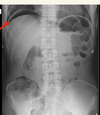

what are these lines in these bowl obstructions. where are each of the obstructions?

what is the red arrow pointing to? what is the likely cause?